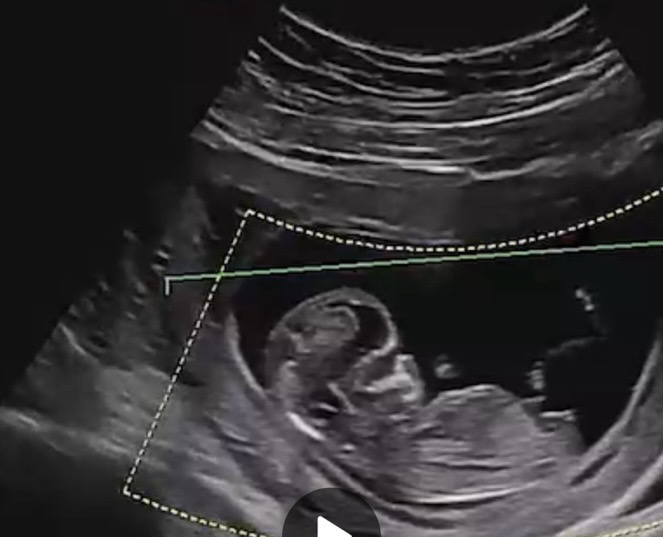

각도법 잘 보시는분!!🫢 12주예욤

건강하게만~~ 이라고 생각하는 반면 성별도 궁금한 마음을 숨길수없네요🥹 동영상 캡쳐본이긴한대 각도가 가장 잘보이는거같아 올립니다🩷

각도법으론 딸같아용